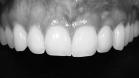

Ein Zahnimplantat ist eine künstliche Zahnwurzel aus Reintitan, die dauerhaft in den Kieferknochen eingesetzt wird. Durch den Prozess der Osseointegration verwächst das Implantat fest mit dem Knochen und bildet eine stabile Basis für Zahnersatz wie Kronen, Brücken oder Prothesen.